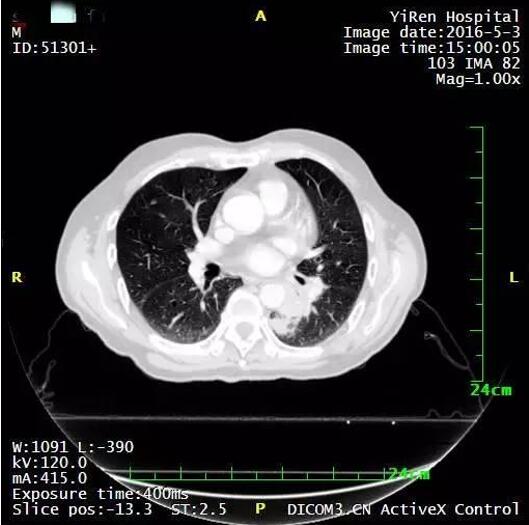

患者男性,64岁。

2016年3月,诊断为小细胞肺癌。

治疗前

治疗后病灶明显缩小

治疗后两个月进一步缩小